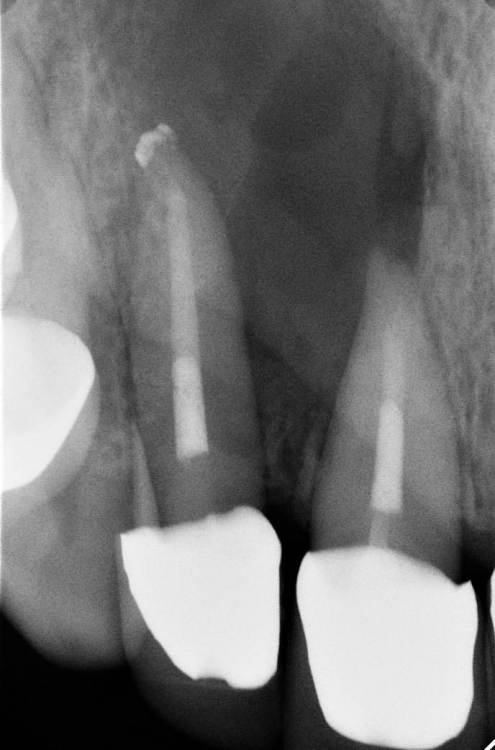

дальше пациент пошла на апикалку, но попала к обычному хирургу, который просто »почикал» корень бором… слегка))

дальше были осмотры каждый год и вот спустя 4,5 лет результат

что скажете?

FD7D4C62-7B6F-4859-8F8A-76F0D9DC3F45.thumb.jpeg.904469e70aa199b70a8e50693a0c468b.jpeg

8729F8B9-7ED7-426E-B615-9A7F76C5F79F.thumb.jpeg.2b6efb9e94e051bbde3dd8994182df8a.jpeg